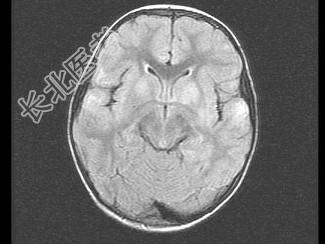

- 单项选择题女,3岁, 头痛、呕吐1周,结合MRI图像, 最可能的诊断是 ( )

A、脑膜炎

B、硬膜下出血

C、脑转移瘤

D、脑梗死

E、脑脓肿